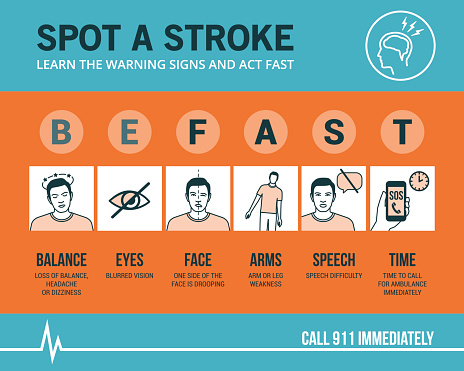

Lacunar infarct is a type of stroke that occurs when one of the arteries supplying blood to the brain gets blocked. These arteries are quite small, which makes them vulnerable to damage. While most arteries in the body gradually become smaller, the arteries of the lacunar stroke branch off a large high-pressure artery. Lacunar stroke ...click here to read more